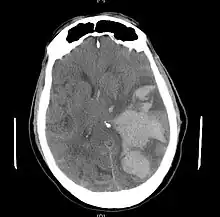

MRI showing damage due to herniation. This person was left with residual disabilities including those involving movement and speech.[15]

Treatment involves removal of the etiologic mass and decompressive craniectomy. Brain herniation can cause severe disability or death. In fact, when herniation is visible on a CT scan, the prognosis for a meaningful recovery of neurological function is poor.[2] The patient may become paralyzed on the same side as the lesion causing the pressure, or damage to parts of the brain caused by herniation may cause paralysis on the side opposite the lesion.[10] Damage to the midbrain, which contains the reticular activating network which regulates consciousness, will result in coma.[10] Damage to the cardio-respiratory centers in the medulla oblongata will cause respiratory arrest and (secondarily) cardiac arrest.[10] Investigation is underway regarding the use of neuroprotective agents during the prolonged post-traumatic period of brain hypersensitivity associated with the syndrome.[16]